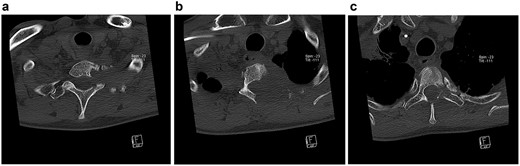

Because of a possible treatment-associated pseudo-progression of the tumor, a watch-wait-procedure was chosen in the interdisciplinary tumor conference. Five months later, CT scans showed an oligo-progression with dorsal tumor growth into the spinal canal, destruction of the Th2 vertebra and infiltration of Th1–3 vertebrae with compression of the corresponding left nerve roots still without any evidence of distant metastasis (Fig. 3).

Transversal CT scans of the thoracic. Extent of bony destruction of the left pedicle, costotransverse joint and facet joint of C7/Th1 (a), the left hemilamina, pedicle, costotransverse facet joints, rib and vertebral body of Th2 (b) and hemilamina as well as pedicle of Th3 (c).